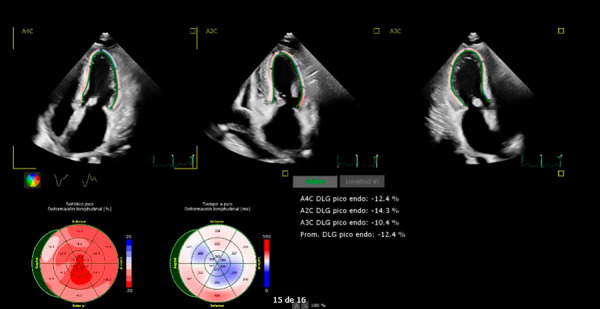

我们报告一例全身轻链淀粉样变性与心脏累及,之前单克隆IgG λ γ病。临床诊断是基于心衰的迹象,心脏生物标志物升高,和特征性影像学发现。血液和尿液中游离轻链水平升高,脐周脂肪和胃肠道多节段出现淀粉样蛋白沉积,证实了诊断。开始使用达拉单抗、硼替佐米和地塞米松治疗,在诊断22个月后进行自体造血干细胞移植,获得了良好的临床结果。

We report a case of systemic light chain amyloidosis with cardiac involvement, preceded by a monoclonal IgG lambda gammopathy. The clinical diagnosis was based on signs of heart failure, elevated cardiac biomarkers, and characteristic imaging findings. The diagnosis was confirmed by increased levels of free light chains in blood and urine, as well as the presence of amyloid deposits in periumbilical fat and multiple segments of the gastrointestinal tract. Treatment with daratumumab, bortezomib, and dexamethasone was initiated, followed by autologous hematopoietic stem cell transplantation 22 months after diagnosis, resulting in a favourable clinical outcome.